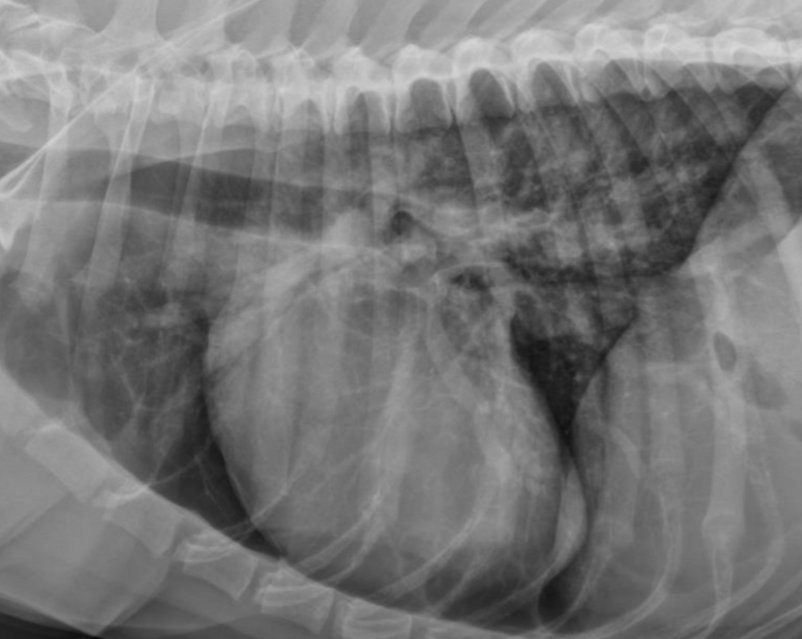

What part of the heart is enlarged?

LVE (technically LAE too) - prof used the same photo for both but outlined different features

3 features of LVE VD

-elongation of cardiac silhouette

-deviation of apex to the left

-bulge at 3-5 o’clock

LVE